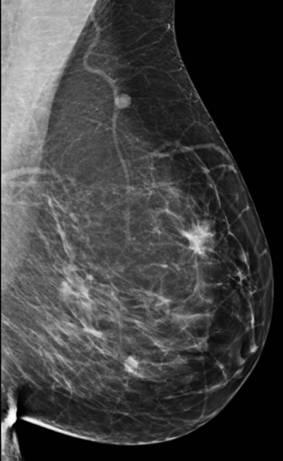

Ung thư vú

» Thông tin: Nữ giới – 56 tuổi.

» Lâm sàng: Khối tuyến vú.